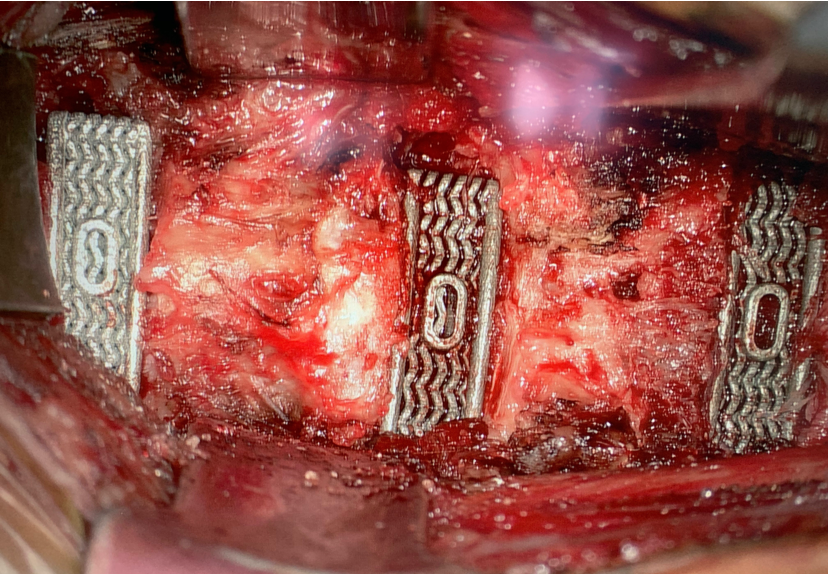

Nexus Spine is excited to share pilot study results of a comparative radiographic assessment of ACDF outcomes in a series of patients who were selected for common risk factors of subsidence, instability, and delayed bone growth. Specifically, the patients were over 66 years of age, had poor bone quality, and/or required cervical fusion surgery at three or more contiguous levels. Each patient received a Nexus Spine Tranquil® cervical interbody cage at one or more spinal levels, and, as a control, some patients received one or more competing interbody devices at adjacent level(s).

Post-operative radiographic assessment of the treated levels at each of two weeks, six weeks, six months, and twelve months revealed that the levels treated with Nexus Spine’s Tranquil® interbody devices had no measurable subsidence. In contrast, the levels treated with the other interbody devices demonstrated measurable subsidence as soon as two weeks in more than 66% of the levels treated. Subsidence is a primary indicator of spinal instability and pain. Accordingly, the results of this study suggest that Nexus Spine’s patented technology amounts to a significant improvement over the competing devices.

Another compelling result of the study is that each of the patients experienced total maintenance of restored disc height and sagittal alignment at all levels treated with Tranquil® cervical interbody cages. This is exceptional when compared to the levels treated with competitive cages, which experienced subsidence. Also, peer-reviewed publications demonstrate competitive devices that exhibit at least 3 mm of subsidence in more than 52% of patients. Nexus Spine’s Tranquil® interbody cages performed much better, with no subsidence.